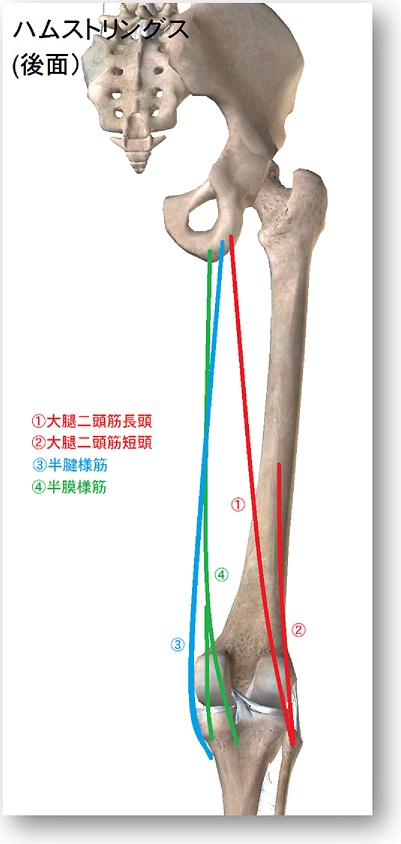

大阪市東成区今里にあります鍼灸治療院リーチです。つったり肉離れを起こしたりする大腿二頭筋 についての考察です。

大腿二頭筋は太ももの裏側にあります。

半健半膜様筋とともに

「ハムストリングス」

とも呼ばれます。

長頭と単頭があり

長頭は坐骨結節から始まり

股関節・膝関節にまたがる二関節筋で

短頭は大腿骨後面の粗線から始まる

単関節筋です。

長頭・短頭は浅層深層の関係になります。

両方とも腓骨頭の外側に停止します。

膝裏の外側のピンと張った部分(膝を曲げると持ち上がってくる部分)が長頭の腱にあたります。

ハムストリングス

内側の半腱半膜様筋と合わせて

ハムストリングス

と呼ばれることがあります。